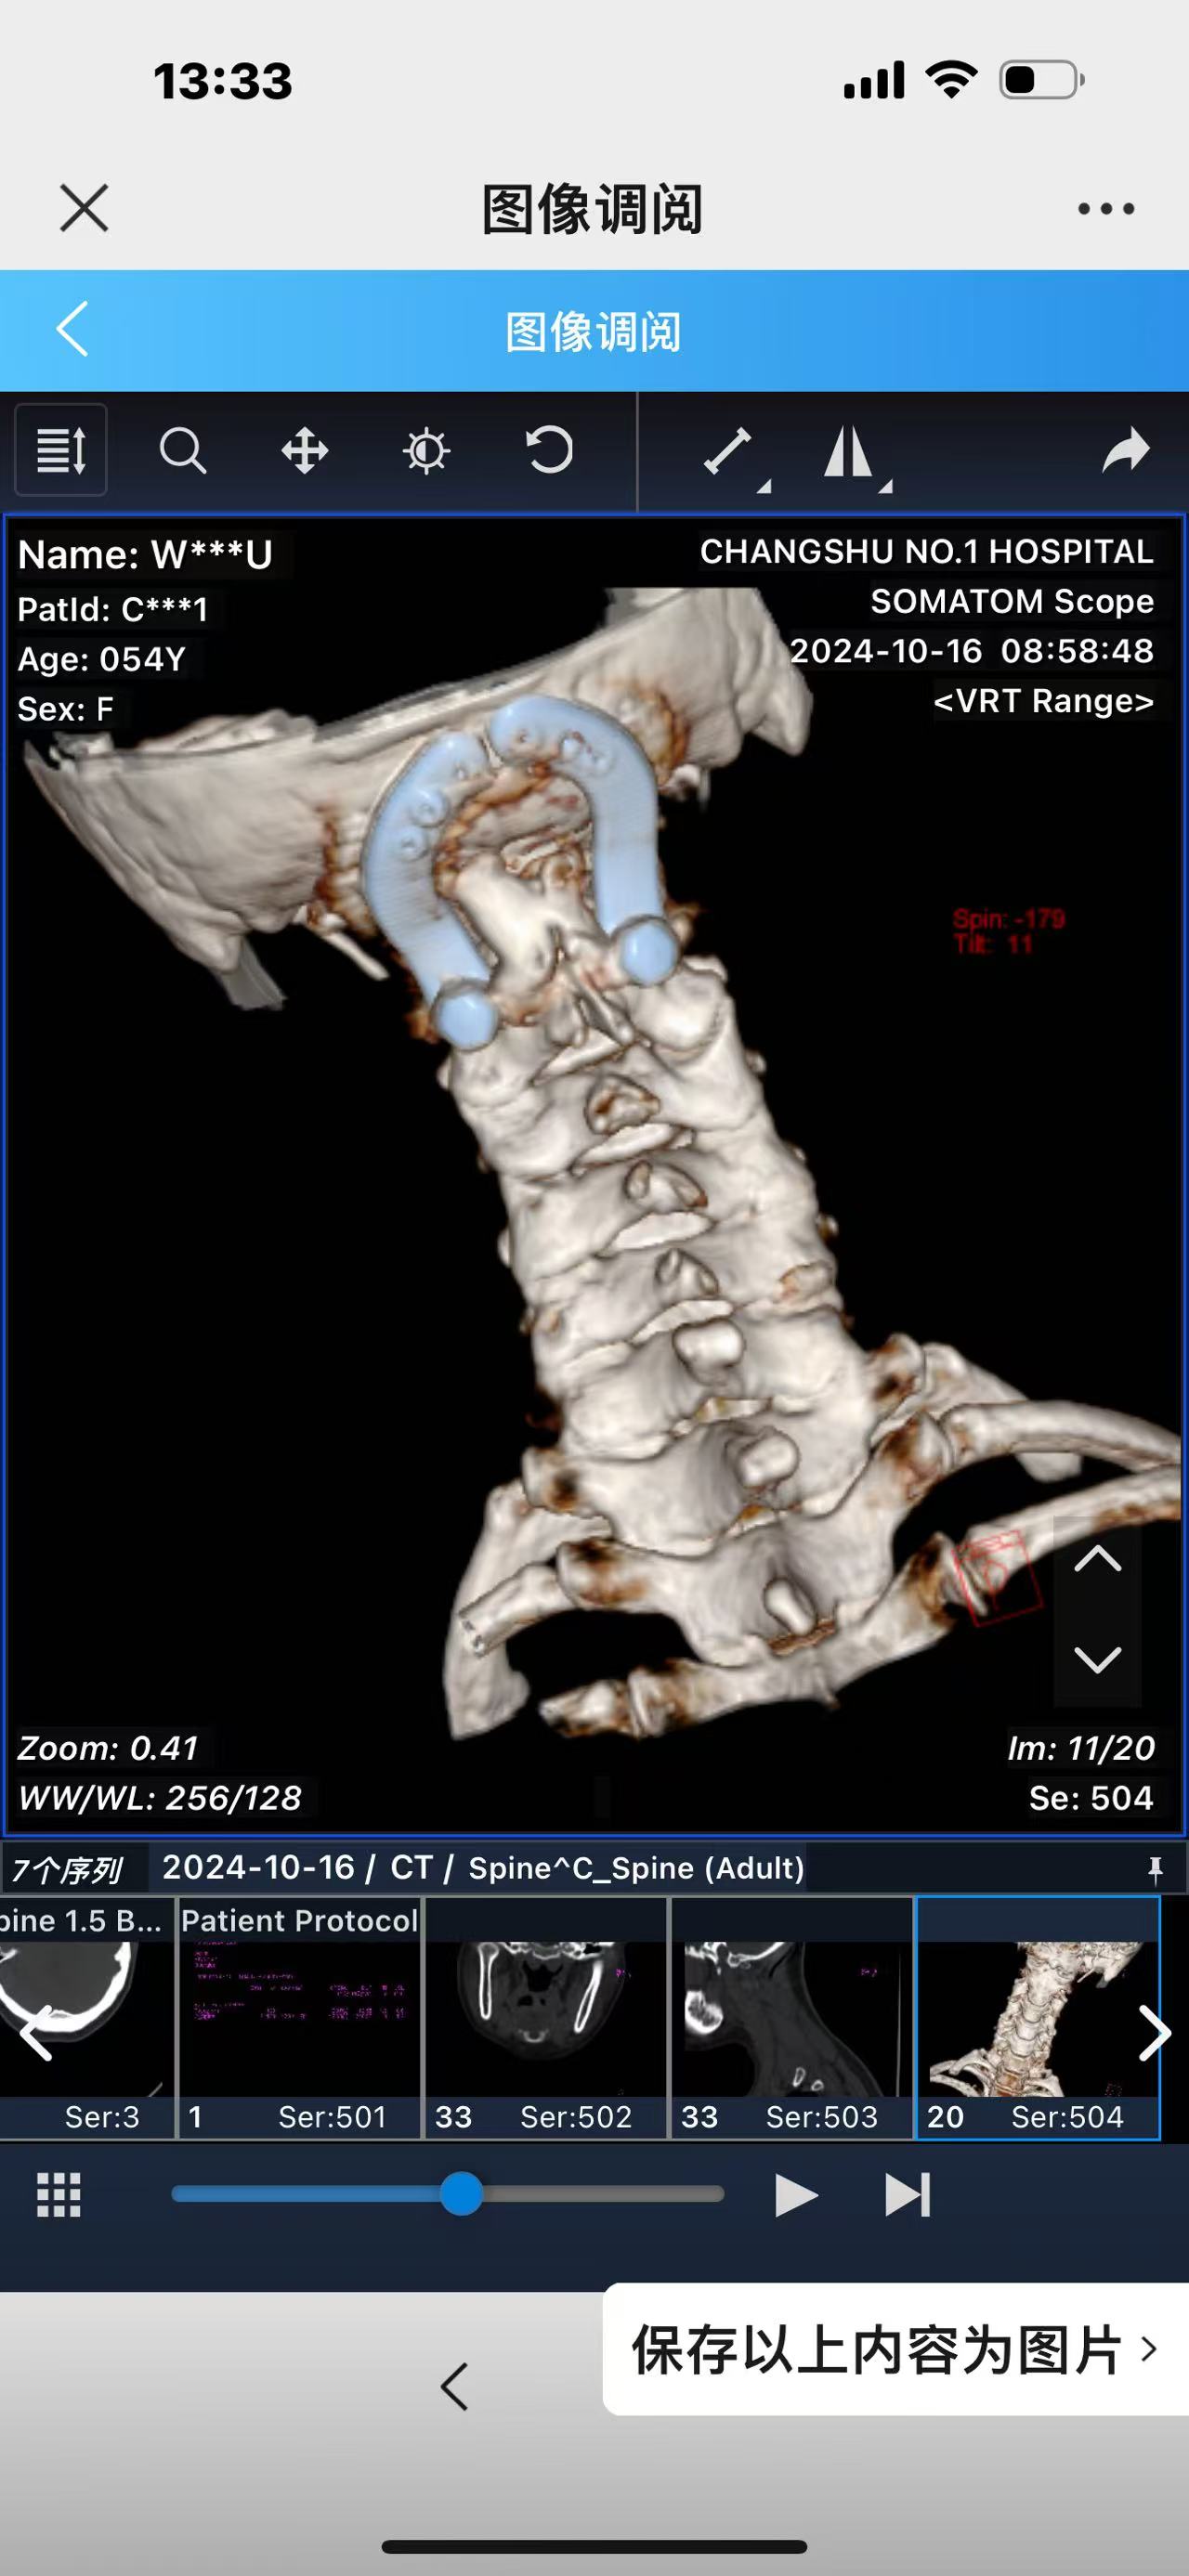

• 诊断:寰枢椎脱位,颅底凹陷

• 术后影像:

• 2024.10.20,复查,对位良好,偶尔会肩甲骨酸,坐下就不酸。